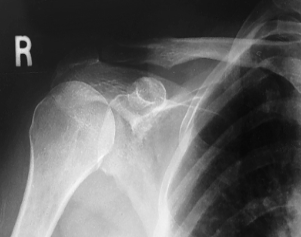

is this a normal or dislocated shoulder? in which direction is it dislocated?

dislocated, anterior